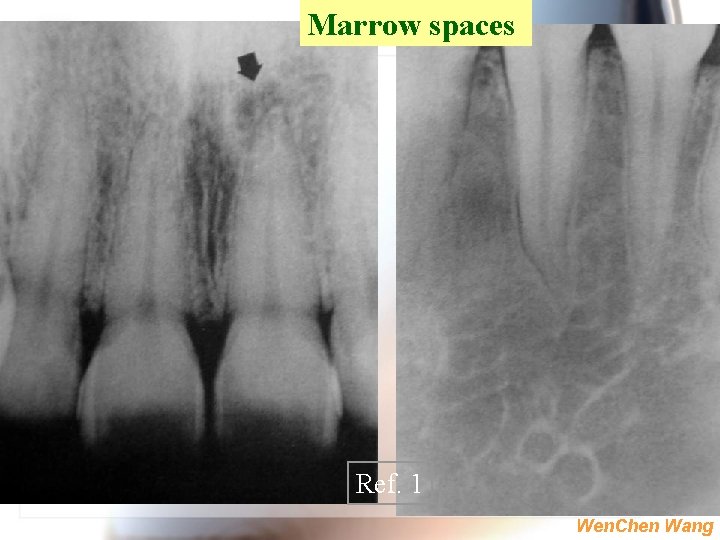

Marrow spaces Ref. 1 Wen. Chen Wang